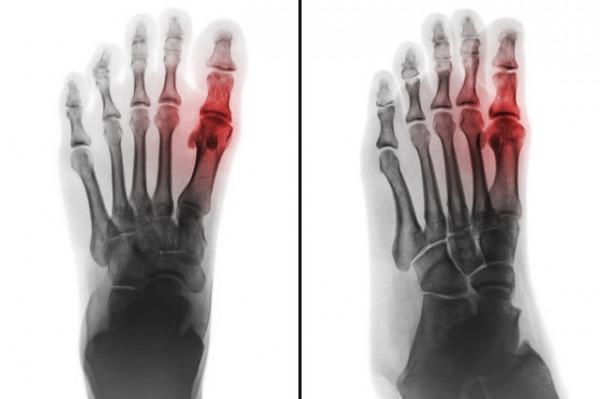

首先我們先了解一下痛風,痛風是因嘌呤代謝障礙引起的代謝性疾病,當血中尿酸濃度過高和(或)在酸性環境下,尿酸可析出結晶,沉積在關節內,引起痛風性關節炎。

痛風急性發作是因尿酸代謝異常誘發的區域性無菌性炎症反應,與細菌感染無關,所以吃頭孢類、青黴素類等“消炎藥”不會有作用!